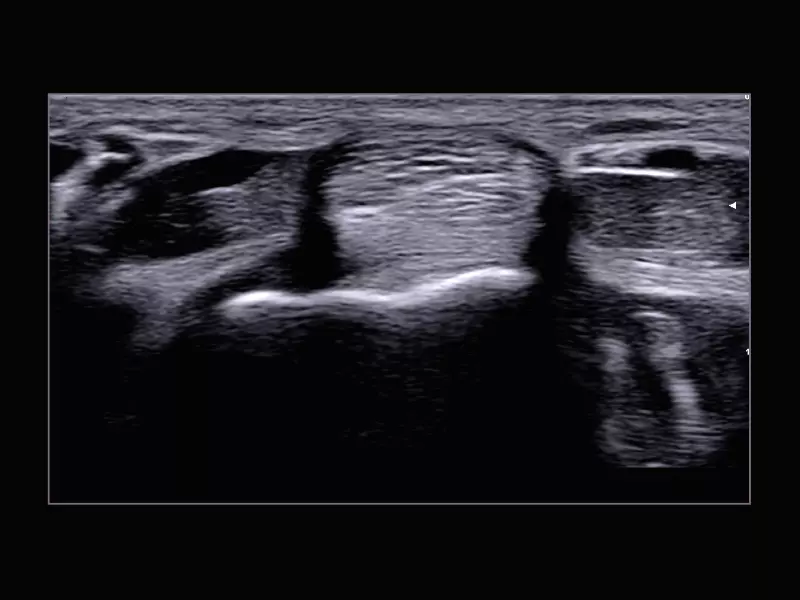

MyLab™Sigma Elite - Power Doppler on acute polyarthritis inflammation area with 18 MHz probe

MyLab™Sigma Elite - Power Doppler on acute polyarthritis inflammation area with 18 MHz probe